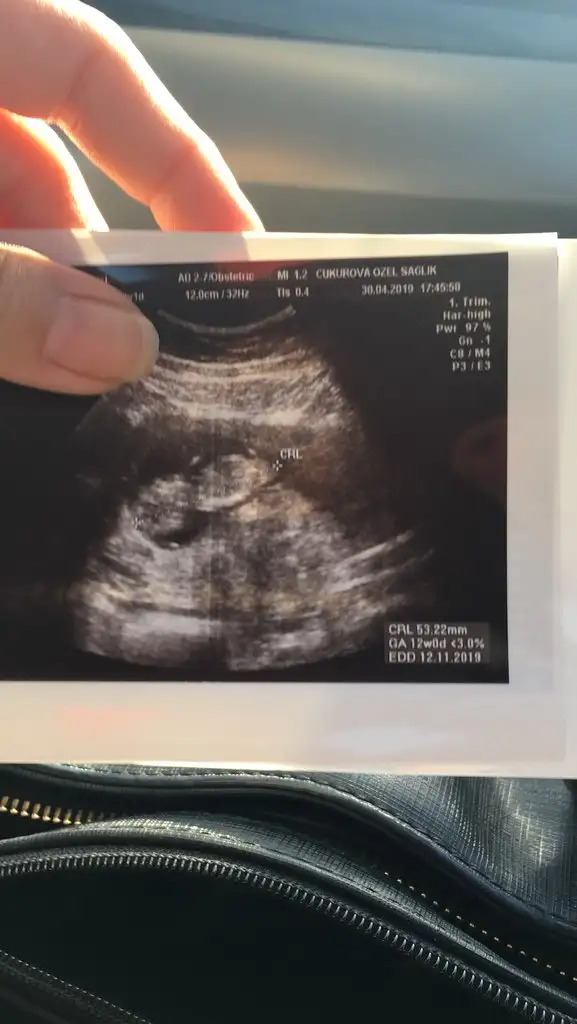

Merhaba canim..Eve yeni geldim..Cok sukur guzel gecti.Her seyi normal..Ense kalinligi iyi dedi doktorum.Suyun da yeterli dedi.Ayrintili olarak bakti.Masallah bir sorun yok dedi. 12 hafta 1 gunluk..Ikili test icin kan alindi.Kalp atisini da duyduk.O da iyi,ritmik dedi..Şukurler olsun bir problem gozukmuyor.Cinsiyet icin tam belli degil kesin bir sey soyleyemem ama erkege benziyor ama kordon da olabilir dedi.Bunlar da resimleri..Cinsiyet tahminlerini bekliyorum kizlar.:))

Eklentiler

• 20190430_185108.webp

20190430_185108.webp

21,1 KB · Görüntüleme: 63

• 20190430_185008.webp

20190430_185008.webp

20,6 KB · Görüntüleme: 63

• 20190430_185031.webp

20190430_185031.webp

12,5 KB · Görüntüleme: 57